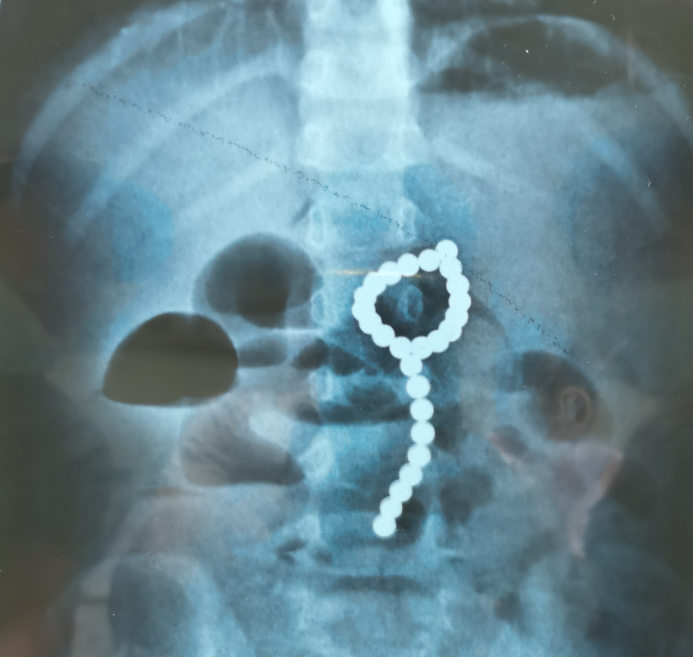

4歲女孩吞下26顆磁力珠 腸道磨穿6個(gè)洞

拍片顯示女孩腹部有一串珠子。武漢兒童醫(yī)供圖

女孩晚餐后叫“肚子痛”,到醫(yī)院一查發(fā)現(xiàn)肚子里居然有26顆磁力珠!醫(yī)生全力救治,將珠子全部取出,并將孩子胃腸道被磨破的6處“破洞”修補(bǔ)完整。

4歲女孩莎莎(化名)平時(shí)健康活潑,家住鄂南地區(qū)。8月11日晚上,她吃晚飯后總說(shuō)“肚子痛”,疼得厲害時(shí)大汗淋漓,還吐了幾次。家長(zhǎng)擔(dān)心是吃壞了肚子,就莎莎帶到當(dāng)?shù)蒯t(yī)院就診。拍片發(fā)現(xiàn),莎莎腹部有異常高密度陰影,看形狀像是一顆一顆的小珠子,一數(shù)有26顆。在父母的追問(wèn)下,莎莎才說(shuō)她吞了“彩色的小珠珠”,推測(cè)應(yīng)該是家里的玩具磁力珠。

外科醫(yī)生在莎莎胃內(nèi)共找到了26顆磁力珠并順利取出,和當(dāng)?shù)貦z查數(shù)目一致。擔(dān)心影像片有重疊導(dǎo)致有“漏網(wǎng)之魚(yú)”,醫(yī)生術(shù)中再給莎莎拍胸腹部X片,好在沒(méi)有新的發(fā)現(xiàn)。之后,醫(yī)生繼續(xù)探查腸道共發(fā)現(xiàn)六處穿孔,逐一精心修補(bǔ)。